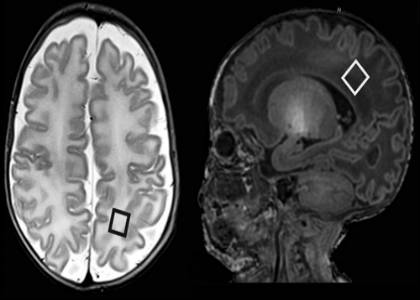

Patients in the study included 43 infants (24 male) born at less than 32 weeks gestation and admitted to the neonatal intensive care unit (NICU) at the University College of London between 2007 and 2010. Dr. Kendall and his research team performed magnetic resonance imaging (MRI) and MR spectroscopy (MRS) exams on the infants at their approximate expected due dates (or term-equivalent age). MRS measures chemical levels in the brain.

The imaging studies were focused on the white matter of the brain, which is composed of nerve fibers that connect the functional centers of the brain.

Statistical analysis of the MRS results and Bayley Scales scores revealed that the presence of two chemical ratios—increased choline/creatine (Cho/Cr) and decreased N-acetylaspartate/choline (NAA/Cho)—at birth were significantly correlated with developmental delays one year later.

“Low N-acetylaspartate/choline and rising choline/creatine observed during MRS at the baby’s expected due date predicted with 70 percent certainty which babies were at high risk for motor development problems at one year,” Dr. Kendall said.